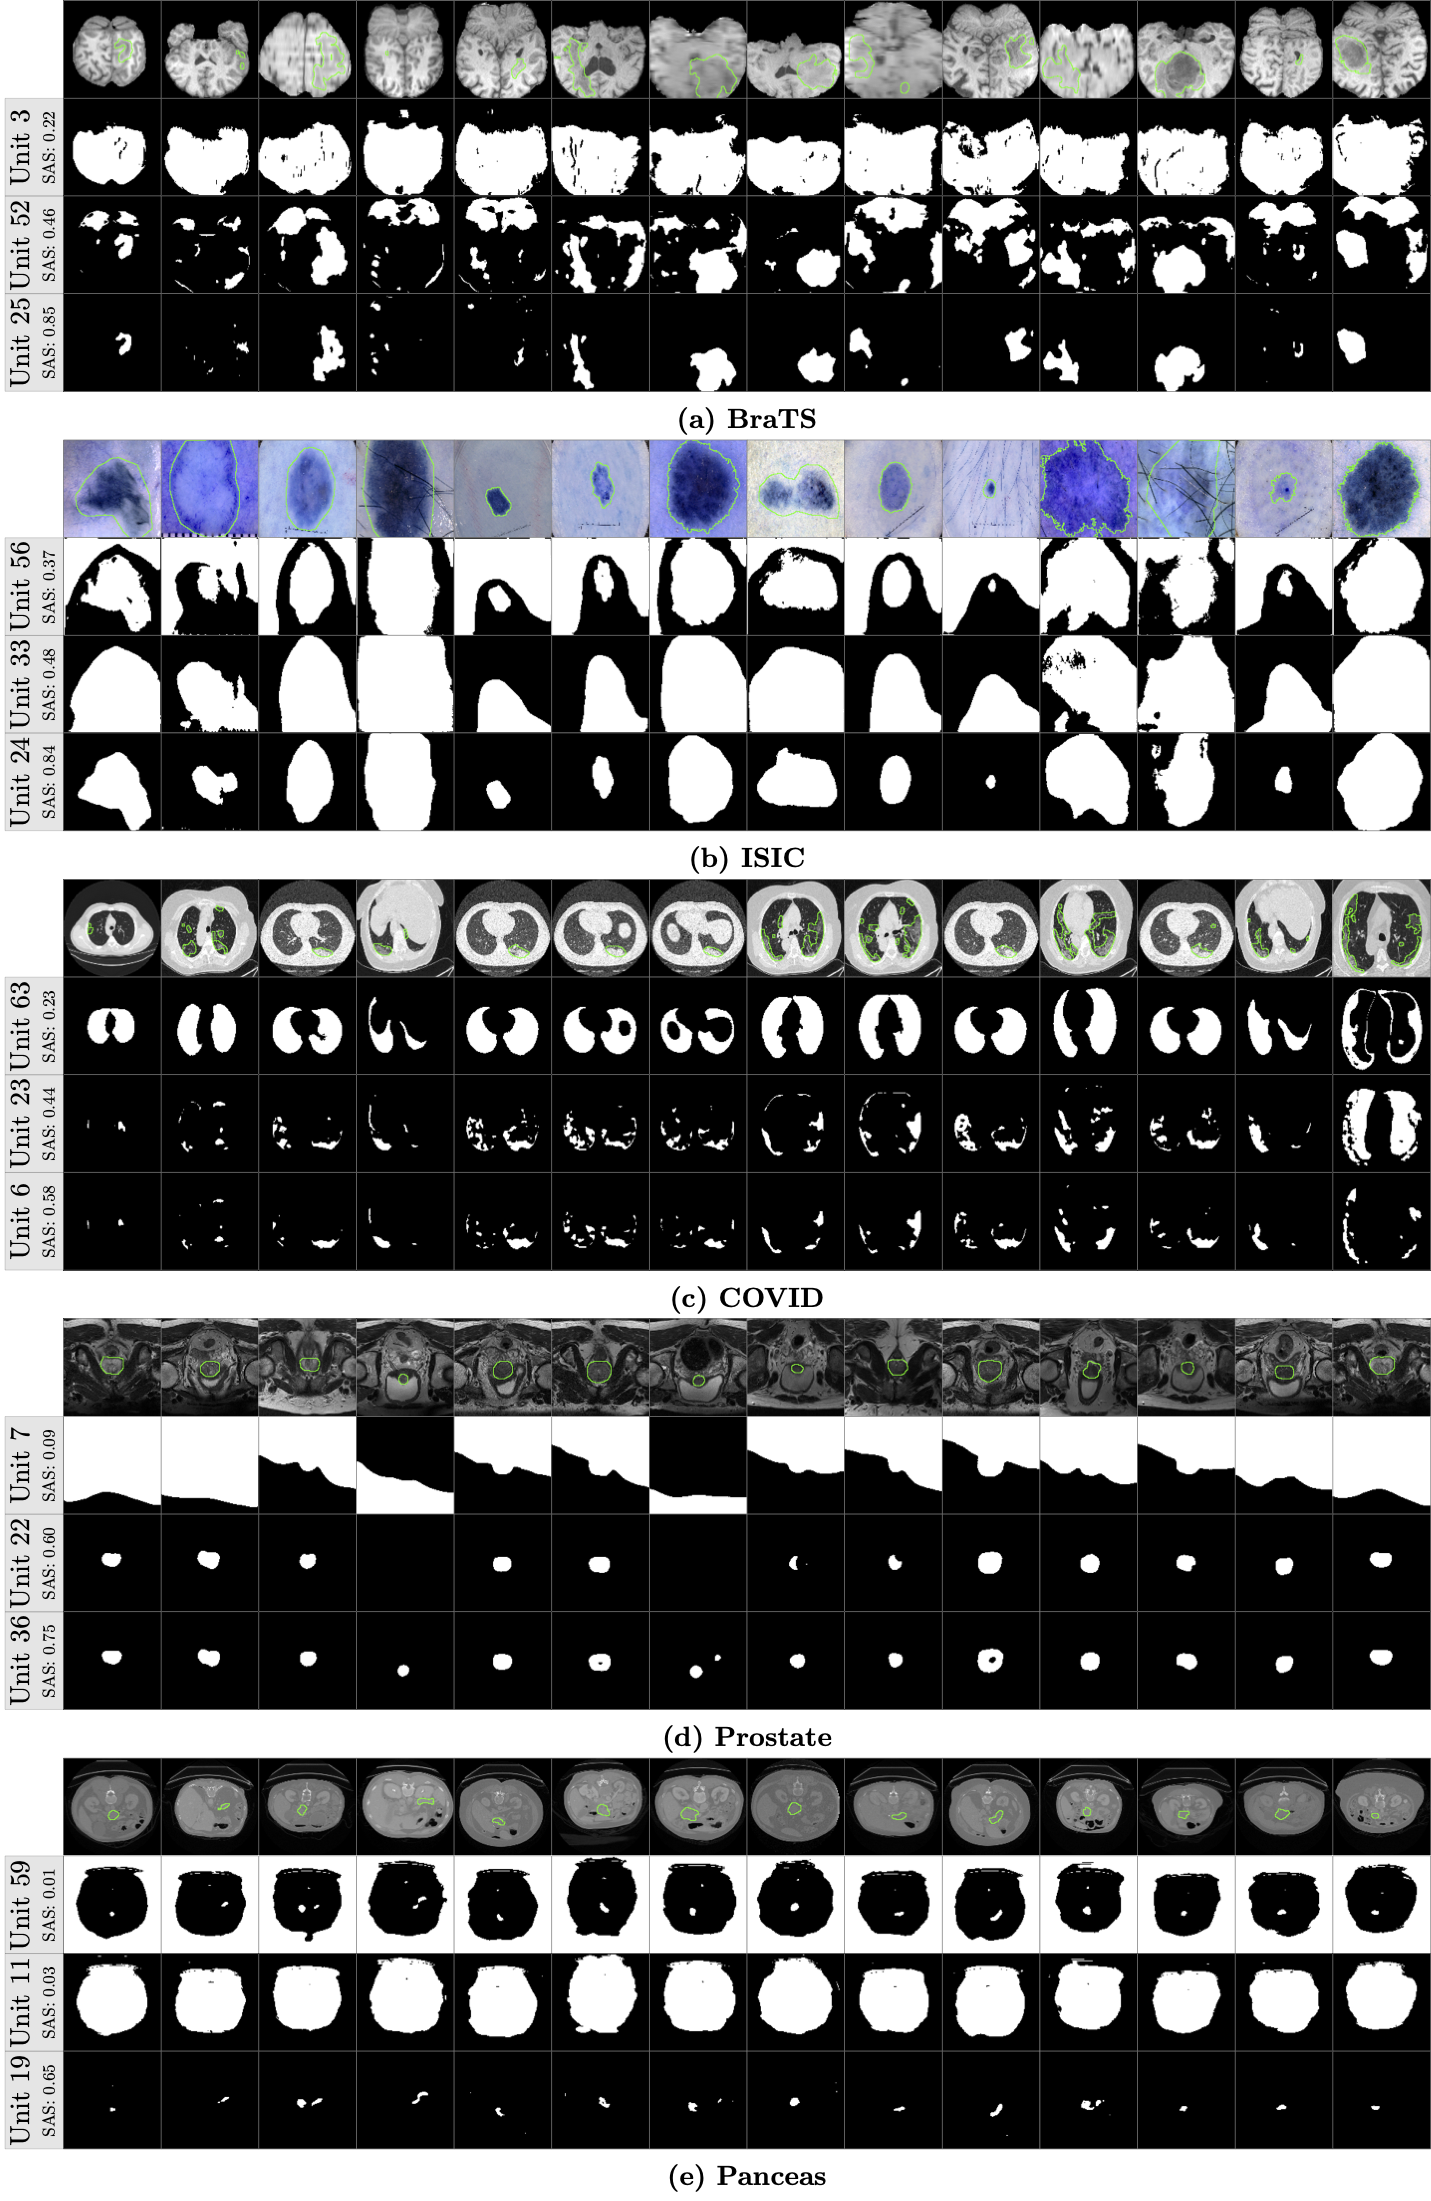

Refer to caption

Figure 8: Several examples of the segmentation maps from different units. The green contours denote the ground-truth and the SAS is the SA score of each unit.

Although our proposed method can evaluate the segmentation ability of units at any layer, we focus on the last layer because the SA score of the last layer is usually higher than other layers (as shown in Fig. 5). There are 64 units on the last convolutional layer (layer 18 in Fig. 4) and it is interesting to know the segmentation ability of these individual units. We extract the deep feature on each unit and use the proposed ProtoSeg to compute the SAM and the SA score. Fig. 7 shows the SA scores of 64 different units on the last layer. The index of the units is meaningless since the weights are randomly initialized. Thus, we sort the units according to their SA scores. It clearly shows that units can be grouped into two parts according to the SA scores and only 20%-50% units have higher SA scores close to the performance of the output. Fig. 8 shows the segmentation maps of several selected units with the lowest, mediate and highest SA scores. Fig. 9 shows the average response (heat-map) of the segmentation maps computed on the units of the last layer. Object pixels/voxels have high values, indicating that most units can separate object regions from the background regions. There is a clear transition from the object regions to the background regions and the pixels/voxels on the boundary of object regions have higher uncertainty values [22].

Our results support the theory that the last layer of the U-Net is heavily oversized and only a part of units have higher discriminative scores [9]. From Fig. 8 we can see that the segmentation maps of the weak units with low SA scores contain both the object and background regions. The SA score of the best unit is similar to the output of the neural network which linearly combines all 64 units on the last layer.